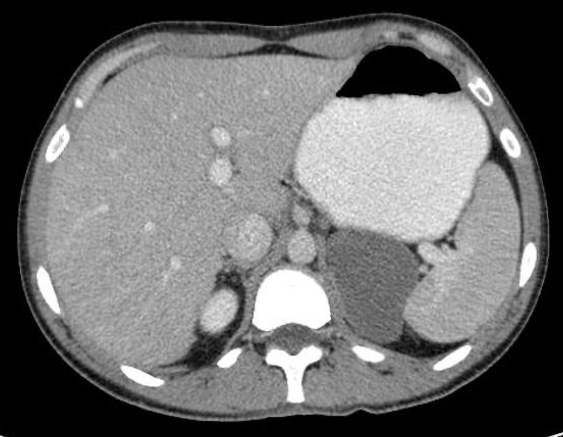

65 anos, Dor abdominal.

Aumento de PCR e VHS.

Mesenterite esclerosante (paniculte, mesenterite retrátil)

Doença crônica idiopática inflamatória da gordura mesentérica. Predomínio em idosos;

Sinal do mesentério enevoado: densificação da gordura com formação de uma pseudocápsula; poupa a gordura ao redor dos vasos do mesentério; pode ter linfonodos mesentéricos aumentados;

Pode estar associado à malignidade como câncer de mama, pulmão, linfoma;

Tratamento inicial envolve corticoterapia; Seguimento envolve queda dos marcadores inflamatórios: PCR, VHS.